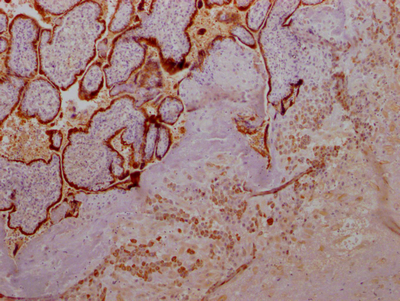

IHC image of CSB-RA891358A0HU diluted at 1:100 and staining in paraffin-embedded human placenta tissue performed on a Leica BondTM system. After dewaxing and hydration, antigen retrieval was mediated by high pressure in a citrate buffer (pH 6.0). Section was blocked with 10% normal goat serum 30min at RT. Then primary antibody (1% BSA) was incubated at 4℃ overnight. The primary is detected by a Goat anti-rabbit IgG polymer labeled by HRP and visualized using 0.05% DAB.

產品描述:CSB-RA891358A0HU人源GH1重組單克隆抗體是針對生長激素1(Growth Hormone 1, GH1)靶點開發的高特異性科研工具。GH1作為垂體前葉分泌的核心蛋白激素,在調節機體生長發育、促進細胞增殖及代謝調控中發揮關鍵作用。本產品經嚴格驗證適用于ELISA和免疫組化(IHC)檢測,其中IHC實驗顯示在1:50-1:200稀釋范圍內能清晰定位人源組織中的GH1蛋白表達,具有優異的組織穿透性和顯色特異性,同時ELISA平臺驗證證實其具備高親和力和低交叉反應性。該抗體采用重組單抗技術制備,具有批次穩定性強、背景干擾低的特點,適用于垂體功能研究、生長發育調控機制探索、代謝相關疾病模型構建等基礎科研領域,特別為組織切片中GH1的空間分布分析及體外定量檢測提供可靠解決方案。

Application Recommended Dilution IHC 1:50-1:200 -